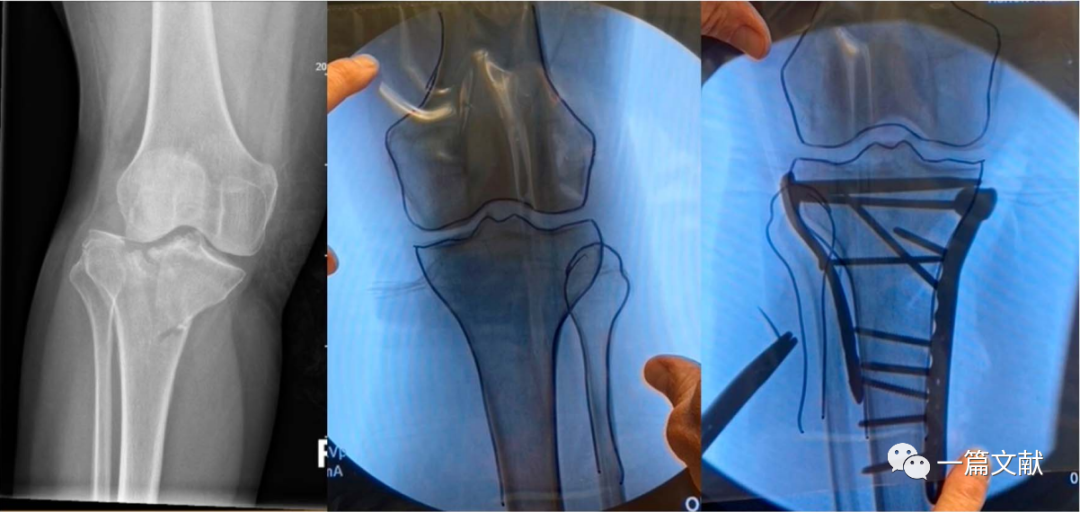

胫骨平台手术

对于累及双侧髁骨折,近端移位明显的骨折尤其有用,如下图: